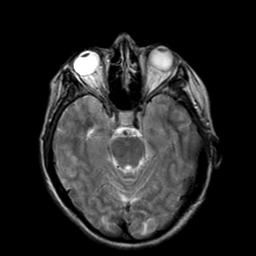

Hypertensive Encephalopathy, overlay -- Slice #8

[Home][Help][Clinical] Slice 8